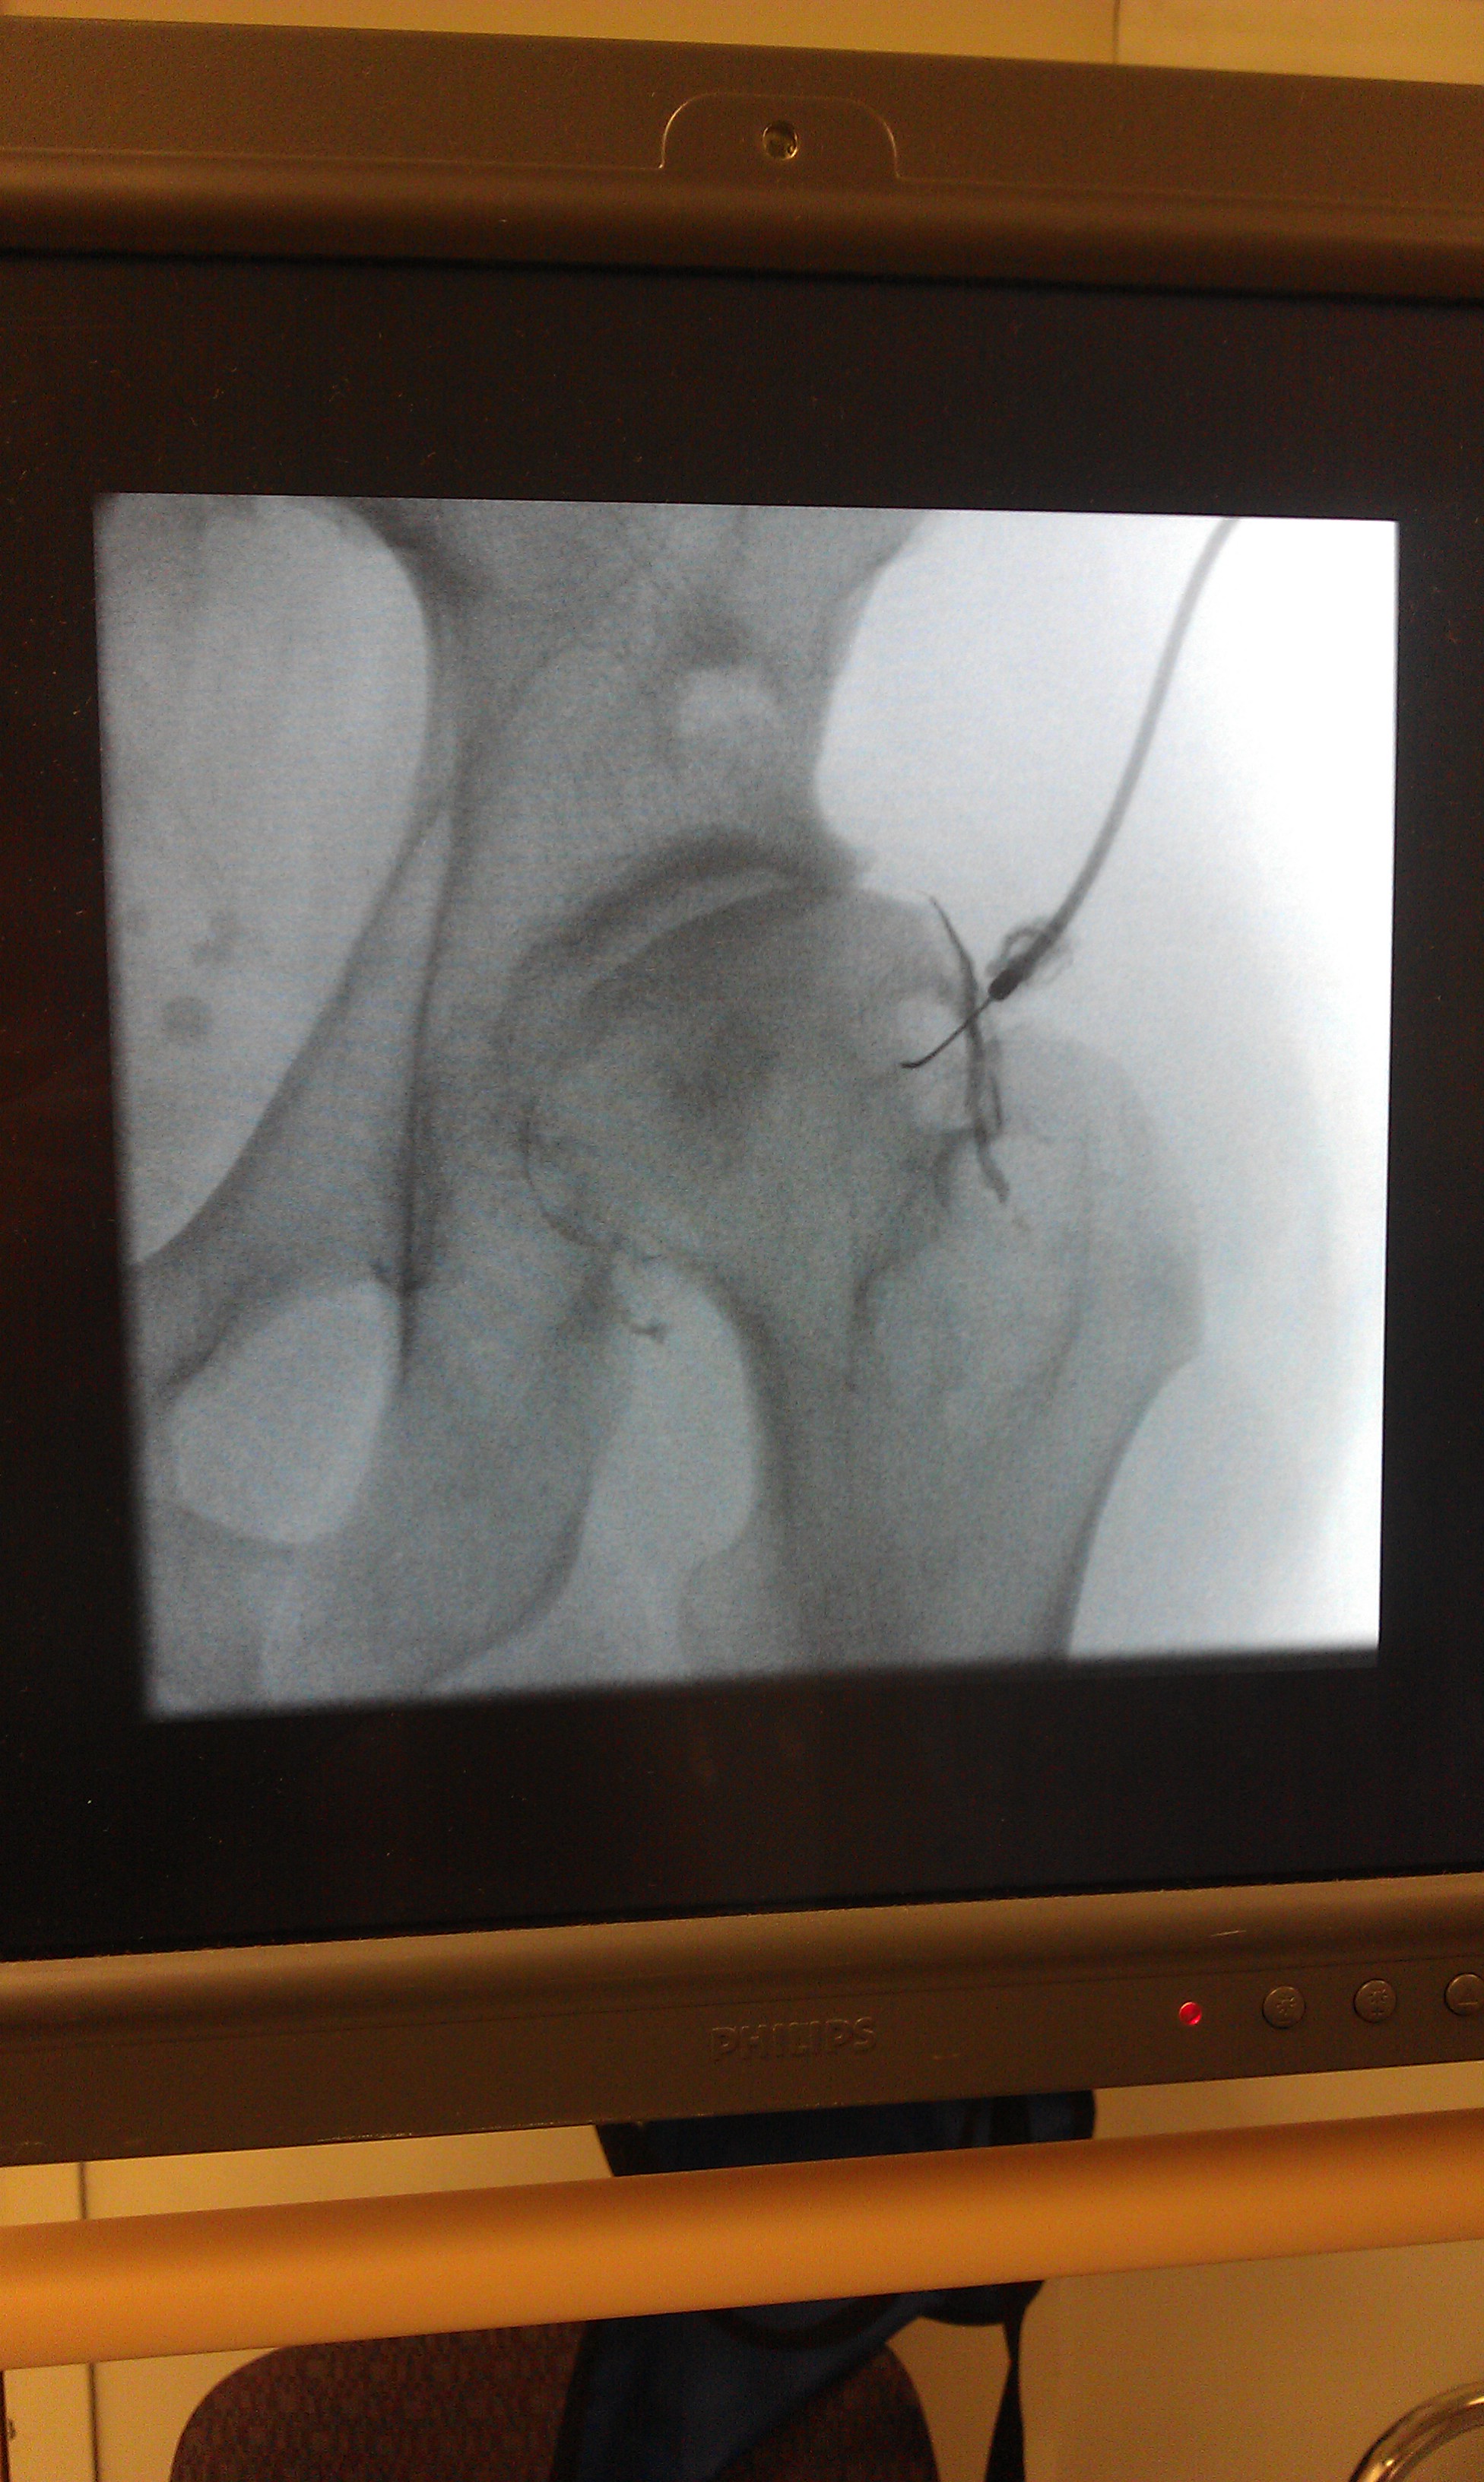

The doctors, every one of them, was stunned to learn that I am only 29 and having a Birmingham Hip Resurfacing, but once they saw my hip x-ray they immediately understood, here is the only photo I could find, from back when I had SynvisicOne injected into the hip, Synvisic is a gel fluid that simulates cartilage when injected in the joint, unfortunately did not work for me. If you look at a side by side images of what a healthy hip looks like you can begin to see all the arthritis, ridges, cracks, and issues with my hip.